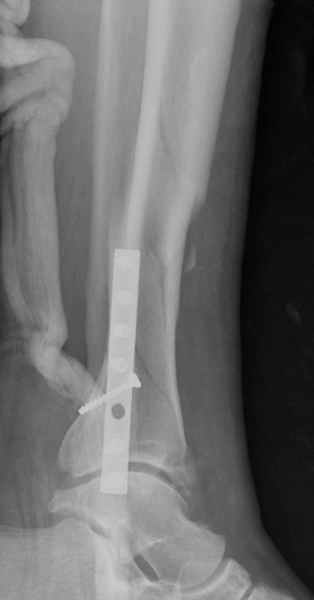

спрашивает что делать с больным который поступил недавно, фермер 55 лет падение при пьяной драке в баре, года два назад перенес операцию на лодыжке, на снимках и КТ перелом без вовлечения сустава,